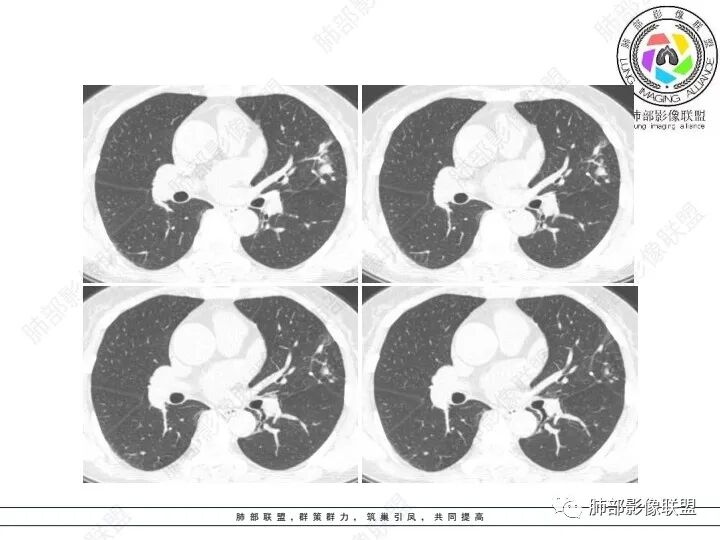

1、临床特点:61岁女性,体检发现肺结节。

2、影像特点:左肺上叶不规则病灶,冠状位、矢状位、斜状位重建显示病 灶整体沿着支气管方向呈斑片状,多结节堆积感明显,病灶大部分边缘显示平直,局部边缘稍膨隆,边界显示比较清楚,近端支气管壁显示增厚,周围可见长索条影及多发结节影,未显示典型“树芽征”。邻近叶间裂未受牵拉凹陷。纵隔窗显示病灶中央可见点状高密度钙化影。

3、病例小结:老年女性体检发现肺部结节,缺乏临床表现,需要警惕恶性。结合影像特点,左肺上叶病灶整体缺乏膨隆感,边缘大多平直,周围多发卫星灶(可见多发长索条影、并非肺CA的细短毛刺),病灶收缩力很弱(邻近叶间裂未见明显凹陷),观察1mm重建图亦可以发现病灶周围没有边界清楚的GGO,病灶内可见钙化点,肺门纵隔未见肿大淋巴结。综合以上,此病灶首先考虑炎性,结核可能性大,有条件可以增强扫描,有助于我们进一步判断。